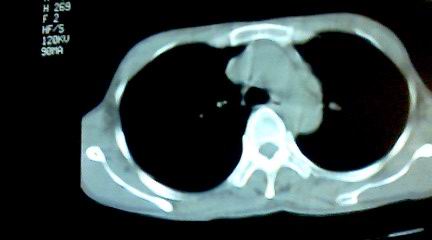

标题: CT25218:请教!胸部CT,胸8椎体骨质破坏,伴周围软组织肿。 [打印本页]

标题: CT25218:请教!胸部CT,胸8椎体骨质破坏,伴周围软组织肿。

患者,女41岁,肢体乏力。

两肺上叶继发性肺结核;胸椎结核并椎旁寒性脓肿形成。

胸椎结核并椎旁寒性脓肿形成。